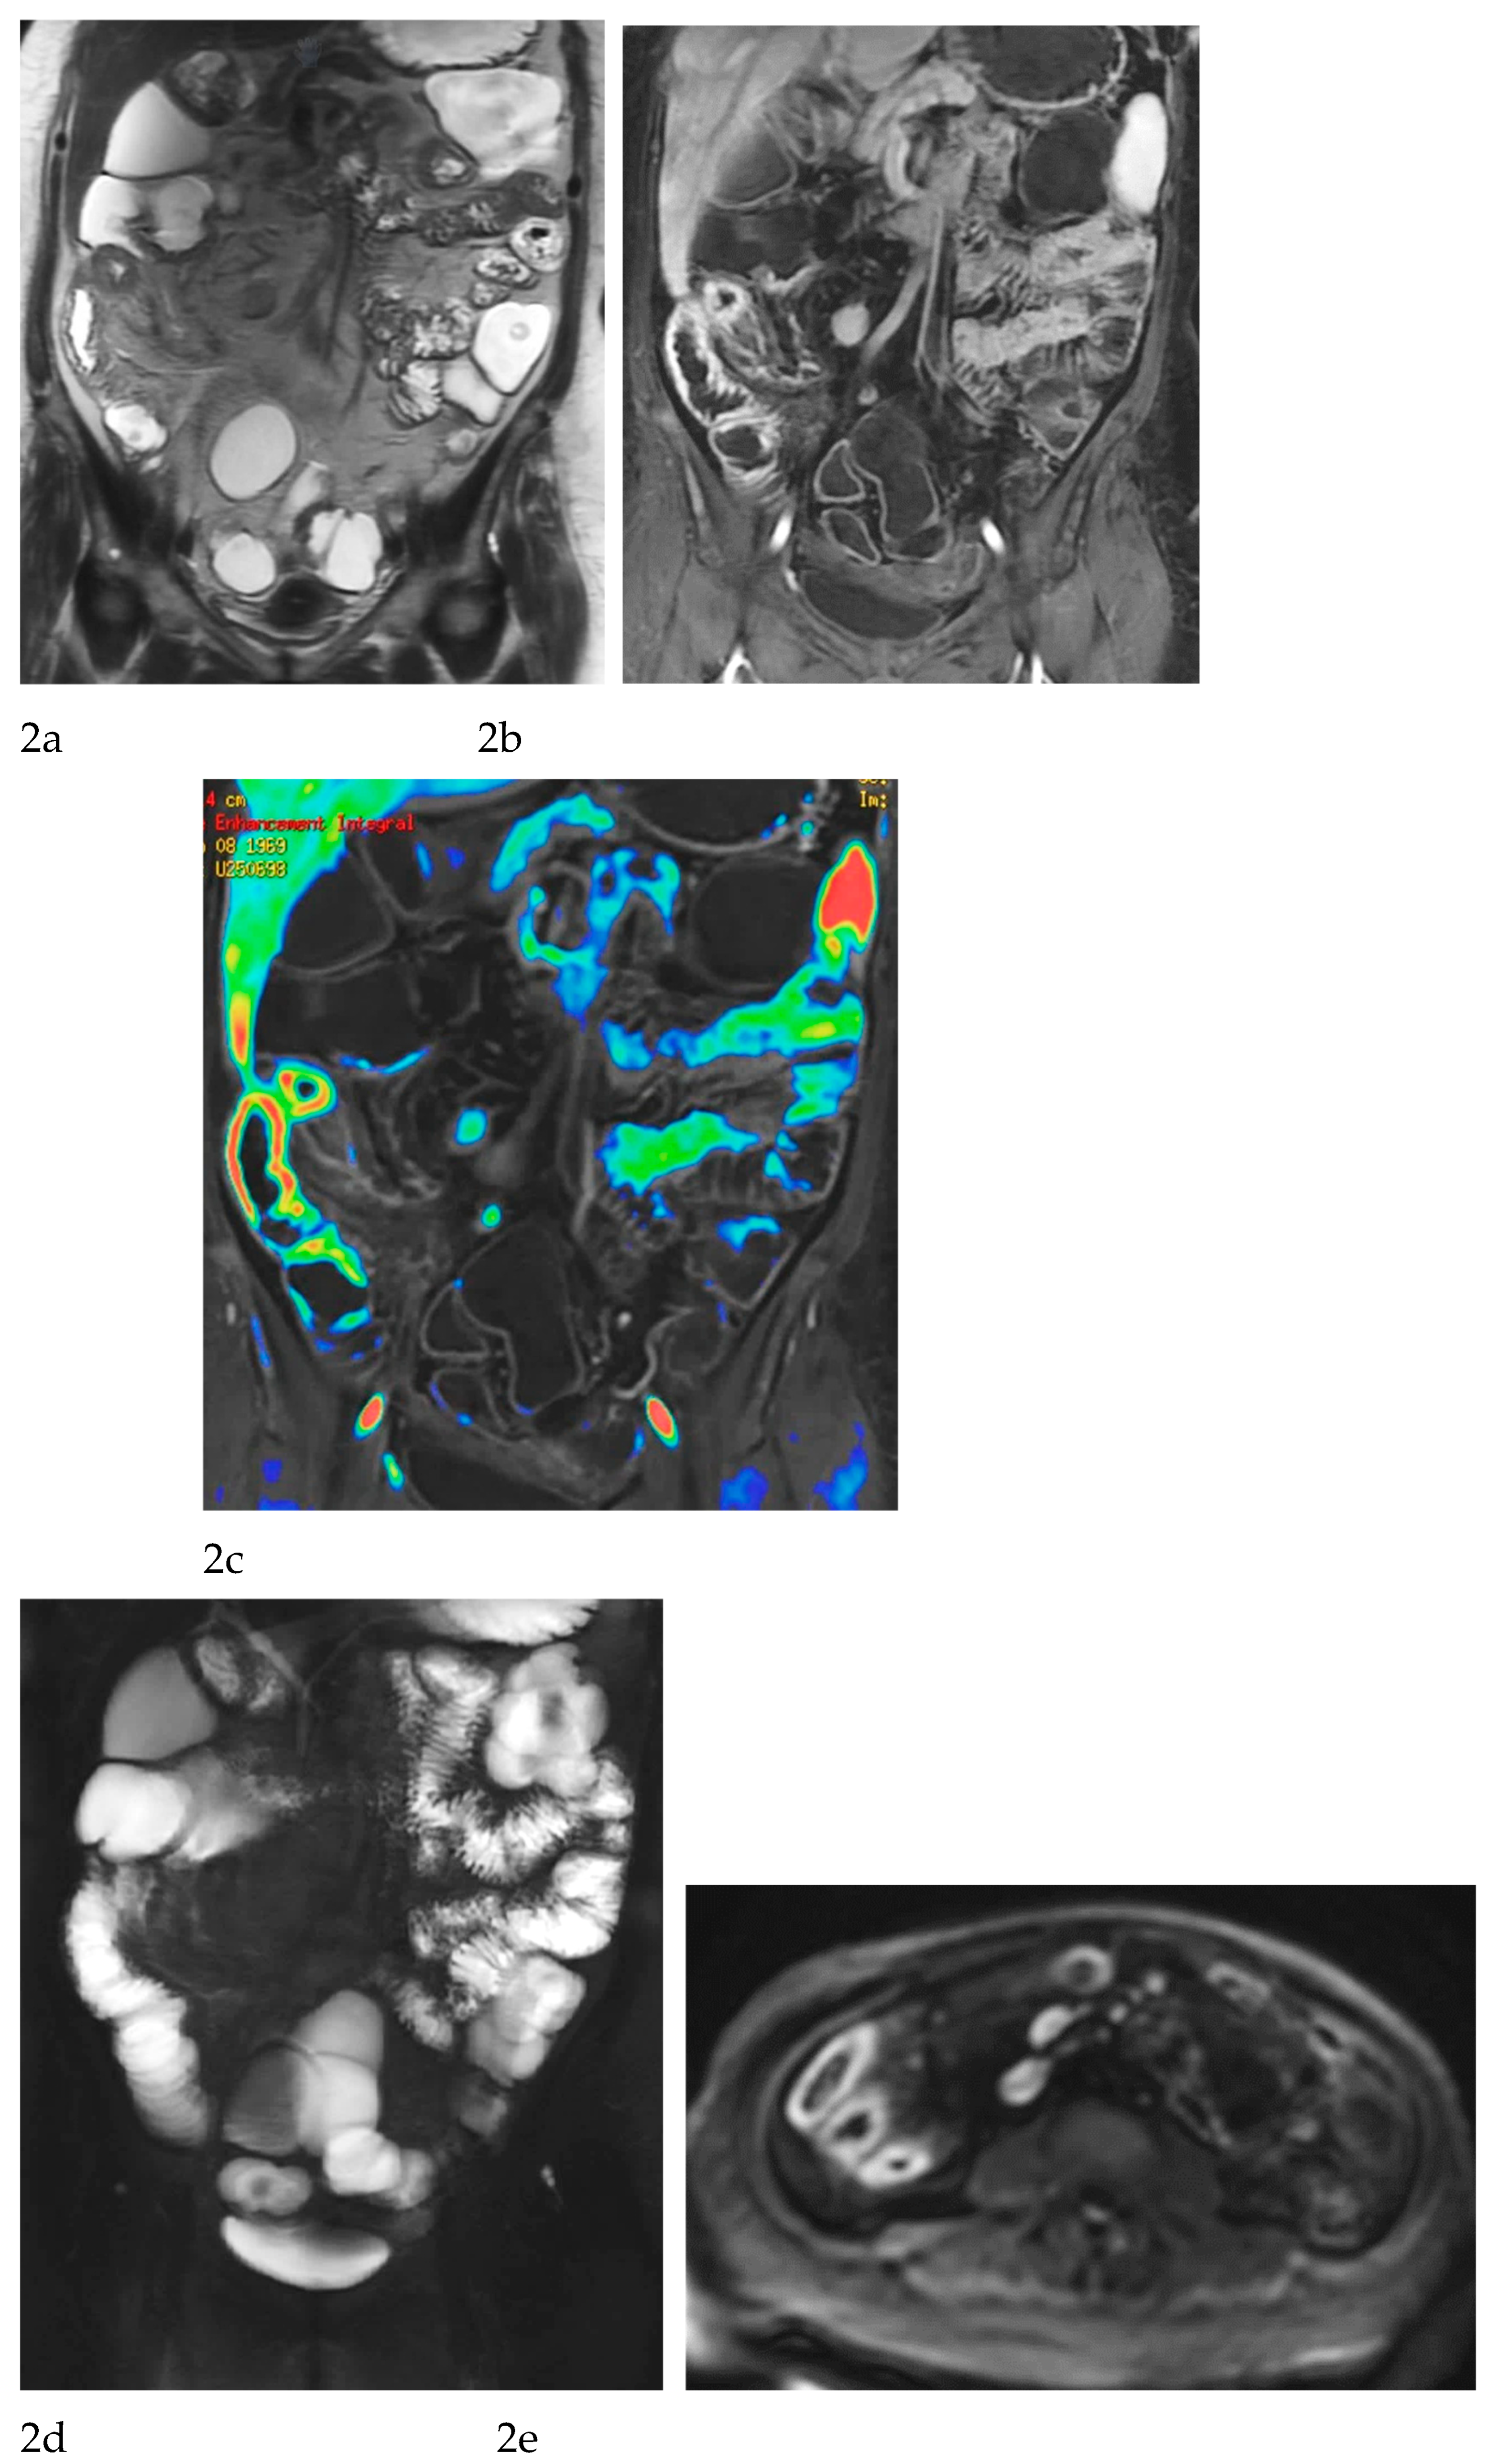

Multiparametric MRE protocols therefore combine a series of complementary sequences, each providing distinct and synergistic diagnostic information. T2-weighted sequences (

Figure 1a-c) are fundamental for a comprehensive morphological assessment of Crohn’s disease on both axial and coronal planes. They allow accurate definition of disease location, longitudinal extent, and severity, including evaluation of bowel wall thickening, luminal narrowing, and the presence of penetrating complications such as fistulas and abscesses at any level of the small and large bowel. These sequences are also essential for assessing extraintestinal manifestations of disease, including inflammatory changes of the surrounding mesenteric fat. Beyond structural assessment, T2-weighted imaging plays a pivotal role in the detection of inflammatory activity through the identification of mural and mesenteric oedema. Fat-suppressed T2-weighted sequences, in particular, enhance the conspicuity of high-signal oedematous tissue and currently represent the only imaging technique capable of directly demonstrating oedema at the level of the intestinal wall, mesenteric lymph nodes, and mesentery. Oedema is a hallmark of active inflammation and reflects increased vascular permeability and interstitial fluid accumulation [

Figure 1d-g), which reflect bowel wall vascularity and the degree of inflammatory activity. These sequences are essential for evaluating not only the affected bowel segments, but also associated inflammatory changes in the mesentery and regional lymph nodes.

In addition, analysis of enhancement behaviour over time is clinically informative: early, intense enhancement is typically associated with active inflammation, whereas delayed and more progressive enhancement may provide indirect information on the presence of fibrotic components within the bowel wall. This temporal evaluation of contrast enhancement therefore contributes to distinguishing predominantly inflammatory disease from mixed or fibrostenotic phenotypes, supporting more tailored therapeutic decision-making. [

MRE is equally valuable in the detection of penetrating complications, an area where its sensitivity rivals or surpasses that of CT [

11]. The modality excels in identifying entero-enteric and entero-colonic fistulas, subtle sinus tracts, intramural or mesenteric abscesses, and inflammatory phlegmons. These complications carry significant prognostic weight, often predicting a more aggressive disease course and influencing therapeutic strategies. Because MRE can evaluate both mural and extramural structures comprehensively, it provides a more complete assessment of disease behaviour than endoscopy alone [

9] (

Figure 1 and

Figure 2).